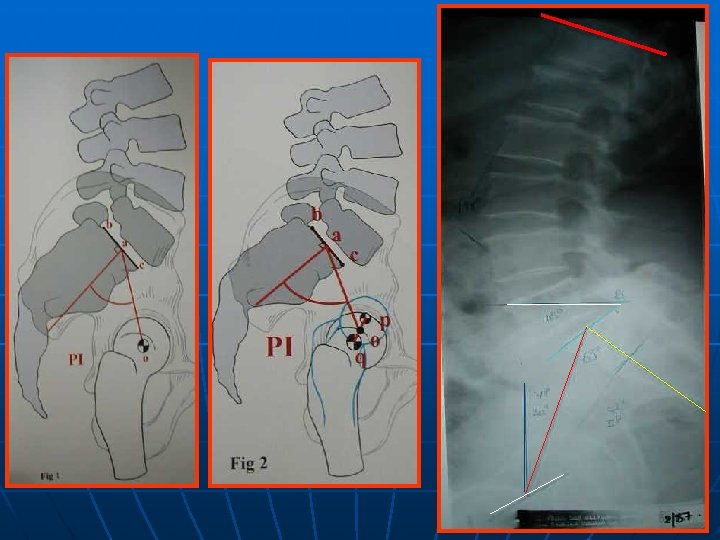

BILAN RADIOLOGIQUE STANDARD +++ *PROFIL : +++ plusieurs paramètres - LL = S 1(L 5)-L 1 ou la vertèbre la plus inclinée! Moy : 60°-64°(L 5 - S 1 : 60 % LL) - IP (incidence pelvienne) = paramètre fixe Angle : milieu tête fémorale- ½ plateau S 1 - perpendiculaire au plateau de S 1 moyenne 50° - P. S. (pente sacrée)= 31 -42° - VP(version pelvienne)=12° IP = PS +VP PS/LL IP/PS